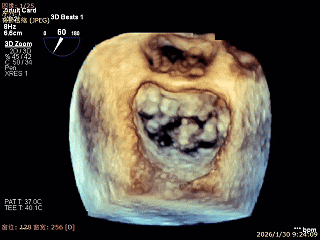

3D Enface 2区及3区前叶脱向左房

3D Enface 可见反流由2区3区从前后冲出

3D Enface下组织桥稳定残余外侧前叶脱垂

3D Enface上彩可见夹子内侧无反流,残余外侧反流

3D Enface下组织桥稳定无反流

夹子释放后,反流基本消失